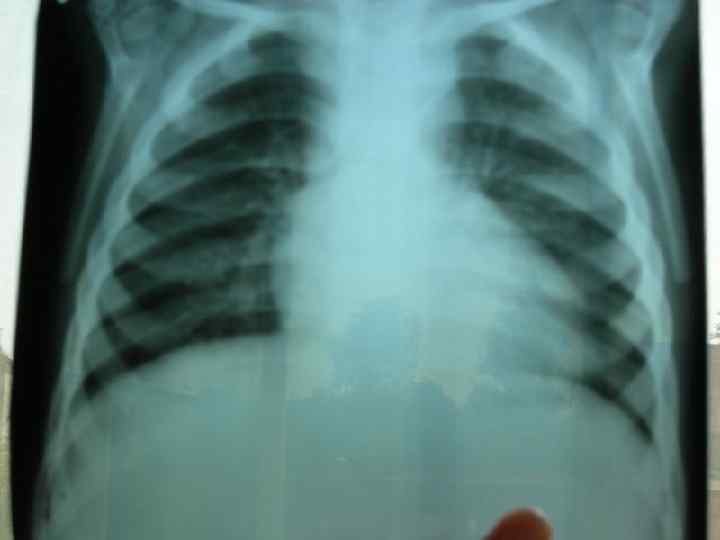

Діагностика ЕКГ: ознаки гіпертрофії ЛШ або обох шлуночків, при склеротичній формі гіпертензії – тільки правого; n Ехо-КГ: візуалізація самого дефекту; n Рентгенологічно: Ш посилення та повнокрів’я легеневого малюнку, розширення коренів легень, збільшення розмірів серця; Ш У період декомпенсації: збіднення легеневого малюнку. n

Диагностика При рентгенологическом исследовании органов грудной клетки описывают форму сердца и состояние легочного рисунка, определяют размер кардиоторакального индекса (КТИ). Все эти показатели имеют свои особенности при разных степенях лёгочной гипертензии. В первой, гиперволемической стадии, выявляется сглаженность талии и погруженность верхушки сердца в диафрагму, увеличение КТИ. Со стороны легочного рисунка отмечается его усиление, нечеткость, размытость. Крайней степенью гиперволемии в лёгких является отёк лёгких. В переходной стадии лёгочной гипертензии отмечается нормализация лёгочного рисунка, некоторая стабилизация размеров КТИ. Для склеротической стадии лёгочной гипертензии характерно значительное увеличение размеров сердца, причем в основном за счёт правых отделов, увеличение правого предсердия (формирование прямого атрио-вазального угла), выбухание дуги лёгочной артерии (индекс Мура более 50%), приподнятость верхушки сердца, которая образует с диафрагмой острый угол. Со стороны лёгочного рисунка часто описывается симптом «обрубленного дерева» : яркие, чёткие, увеличенные корни, на фоне которых лёгочный рисунок прослеживается только до определённого уровня. На периферии имеет место признаки эмфиземы. Грудная клетка имеет вздутую форму, ход ребер горизонтальный, диафрагма уплощена, стоит низко.